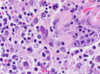

Name & describe the predominant cell type.

Astrocytosis

Gemistocytic astrocytes: plump, reactive astrocytes with eosinophilic cytoplasm